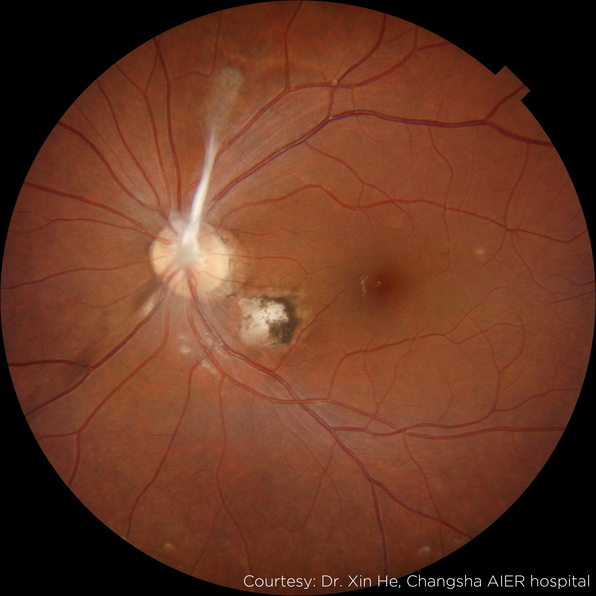

Image Gallery